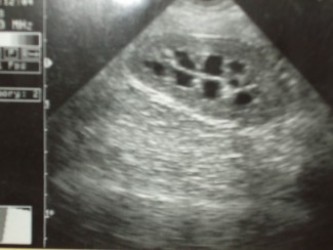

Imagiologia / Ecografia / Raio X